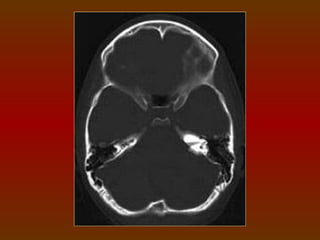

CORTE 9

a) Foice cerebral

b) Sulcos

c) Giros

CORTE 9 a) Foicecerebral b) Sulcos c) Giros